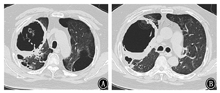

患者短期内双肺出现散在斑片影及斑点影,伴大小不等空洞,考虑肺部感染性疾病。入院后给予比阿培南(0.6 g,静脉滴注,2次/d)+万古霉素(0.5 g,静脉滴注,每8小时1次)联合抗细菌,继续醋酸泼尼松40 mg/d口服抗炎,并给予多索茶碱静脉滴注、雾化吸入布地奈德及特布他林平喘,氨溴索静脉滴注化痰,皮下注射胰岛素控制血糖等治疗。完善相关检查,ESR为47 mm/h;C反应蛋白96.10 mg/L;生化:钾4.0 mmol/L,钠131.0 mmol/L,氯96.0 mmol/L,空腹血糖17.0 mmol/L,尿素7.1 mmol/L,肌酐68.0 μmol/L,丙氨酸氨基转移酶29.0 U/L,天门冬氨酸氨基转移酶13.0 U/L,乳酸脱氢酶253 U/L,肌酸激酶79 U/L,总蛋白51.1 g/L,白蛋白30.8 g/L。尿常规:葡萄糖++++;血结核菌38kD蛋白阴性,结核菌外膜抗体阳性;结核菌素试验阴性;降钙素原、抗链球菌O、类风湿因子、自身抗体系列、肿瘤相关抗原系列、粪常规均正常。术前四项(乙肝表面抗原、丙肝抗体、人类免疫缺陷病毒抗体、梅毒血清特异性抗体)阴性。心电图大致正常。心脏超声:主动脉瓣钙化,左室后壁运动幅度稍减低,左室舒张功能减低。腹部超声:脂肪肝,余未见异常。肺功能:第1秒用力呼气容积/FVC为43.22%,第1秒用力呼气容积占预计值百分比为24.9%,提示阻塞性通气功能障碍,小气道功能障碍,残气量/肺总量轻度增高,弥散功能重度减低。痰涂片找抗酸杆菌阴性(3次)。患者入院当日(2018年1月26日)发热,最高体温达38 ℃;1月27日体温正常;1月28日再次发热,最高体温达38.1 ℃;1月29日之后未再发热,憋喘较前略好转,痰中带血减少。1月29日痰涂片:革兰阳性球菌可见;痰真菌培养:白色假丝酵母菌+。1月30日血1,3-β-D葡聚糖检测(G试验):247.3 μg/L(升高);血常规:白细胞计数12.56×109/L,红细胞计数5.00×1012/L,血红蛋白143 g/L,血小板计数179×109/L,中性粒细胞比例85.3%,淋巴细胞比例7.6%;C反应蛋白55.10 mg/L;血气分析:pH值7.43,PaCO2为48.4 mmHg,PaO2为81.6 mmHg,SaO2为95.8%。入院后每日皮下注射胰岛素累积剂量56 IU。1月26日至1月30日血糖控制不理想,空腹血糖波动于11~18 mmol/L,早餐及午餐后2 h血糖波动于10~18 mmol/L,晚餐后2 h血糖波动于15~21 mmol/L。患者痰检见白色假丝酵母菌+,G试验轻度增高(近期有应用哌拉西林舒巴坦钠史,不排除干扰),近期有糖皮质激素应用史,血糖控制欠佳,综合以上因素,考虑肺真菌感染不排除。1月30日给予伏立康唑200 mg口服抗真菌,每12小时1次(第1个24小时400 mg/次),同时减量醋酸泼尼松为30 mg/d。2月2日痰真菌培养:曲霉菌属+(2次),白色假丝酵母菌+,进一步支持真菌感染,建议行气管镜检查,患者因喘憋不适,一直不同意。之后又有2次痰培养:曲霉菌属1~2个菌落。2月5日患者憋喘较重,复查血常规:白细胞计数23.32×109/L,红细胞计数5.22×1012/L,血红蛋白151 g/L,血小板计数208×109/L,中性粒细胞比例92.2%,淋巴细胞比例3.7%;C反应蛋白229.80 mg/L;血气分析:pH值7.44,PaCO2为47.3 mmHg,PaO2为82.3 mmHg,SaO2为95.7%,提示感染加重。2月5日伏立康唑改为0.3 g,静脉滴注,每12小时1次。2月6日胸部CT示双肺散在斑片影及斑点影,伴大小不等空洞,与1月26日胸部CT比较右肺上叶空洞增大,右肺上叶病变进展(图3)。继续伏立康唑静脉滴注抗真菌,比阿培南联合万古霉素抗细菌治疗。2月12日胸部CT示右肺上叶空洞较2月6日进一步增大(图4)。2月12日血气分析:pH值7.45,PaCO2为57.2 mmHg,PaO2为78.3 mmHg,SaO2为95.1%。经反复动员,2月13日患者同意气管镜检查,结果(图5)示主气管黏膜表面可见白色分泌物附着;左上叶支气管黏膜充血明显,可见大量脓性分泌物;右上叶支气管各叶段开口变窄,以右上叶尖段开口变窄明显;右上叶支气管黏膜充血水肿明显,活检或刷检易出血。气管镜刷片及灌洗液病理见少许坏死物及中性粒细胞,未见肿瘤细胞。支气管镜肺活检(右上叶)病理:送检肺组织慢性炎,肺间质可见单核细胞浸润,纤维组织增生,肺泡上皮增生,肺组织表面附着成团的坏死物,坏死物中可见真菌菌丝及孢子。气管镜刷片培养:曲霉菌属1个菌落;气管镜后痰培养:曲霉菌属4个菌落。患者IPA诊断依据充足,应用伏立康唑效果差,2月14日改为两性霉素B脂质体静脉滴注,从10 mg/d始,逐日递增,增至150 mg/d时患者精神萎靡、憋喘、乏力、纳差、尿少、肾功能异常,尿素18.5 mmol/L,肌酐166 μmol/L,总蛋白45.6 g/L,白蛋白26.9 g/L。2月18日血气分析:pH值7.38,PaCO2为55.4 mmHg,PaO2为72.4 mmHg,SaO2为93.5%。考虑患者对该药不良反应较大,停用两性霉素B脂质体。2月19日给予伏立康唑(0.3 g,静脉滴注,每12小时1次)联合卡泊芬净(50 mg/d,静脉滴注)抗曲霉菌治疗。2月20日后患者多次血气分析示PaCO2升高,波动于56~79 mmHg,PaO2低,波动于50~80 mmHg,给予保肾、人血白蛋白支持、无创呼吸机辅助通气等治疗。口服泼尼松经逐渐减量,于2月17日后停用。住院期间患者一直纳差,进食量少,尽管每日皮下注射胰岛素累积剂量60 IU,但血糖仍控制不理想,空腹血糖波动于12~20 mmol/L,餐后2 h血糖波动于14~26 mmol/L;自停用泼尼松后,血糖逐渐好转,空腹血糖波动于8~10 mmol/L,餐后2 h血糖波动于11~14 mmol/L。3月6日血气分析:pH值7.35,PaCO2为55.4 mmHg,PaO2为72.4 mmHg,SaO2为93.5%。3月6日胸部CT示双肺多发空洞,右肺上叶空洞较前增大,双肺病变继续进展(图6)。治疗效果不理想,家属要求转院。